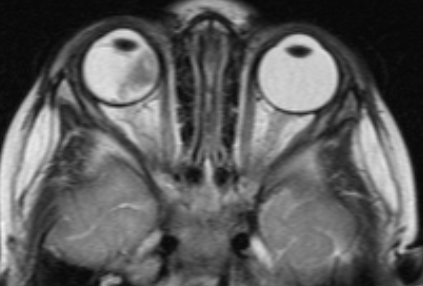

Проведен ретроспективный анализ эффективности лечения детей с различными формами РБ, поступившими в стационар отдела офтальмоонкологии и радиологии МНИИ ГБ им. Гельмгольца с января 2002 г. по декабрь 2006 г. Под наблюдением находились 164 ребенка (79 девочек и 85 мальчиков) с первичной ретинобластомой. Монокулярная форма выявлена у 110 больных (67.0%), бинокулярная – у 54 детей (32.9%), у 1 ребенка выявлена трилатеральная ретинобластома. Наследственная РБ отмечена в 9 случаях (5.5%). Средний возраст больных с монокулярной формой заболевания при обращении составил 28±2.4 мес., при бинокулярном поражении – 14.5±1.5 мес. До госпитализации дети проходили полноценное общеклиническое обследование на предмет исключения регионарных и отдаленных метастазов. Всем детям после года проводили КТ орбит и головного мозга, дети до года подвергались этому обследованию в случае подозрения на экстрабульбарный рост или наличие метастазов в головной мозг. В стационаре все больные были обследованы в условиях медикаментозного сна с максимальным мидриазом, во время которого проводилось полное офтальмологическое обследование, включающее в себя, помимо рутинных методов, осмотр глазного дна ретинальной педиатрической камерой (RetCam), УЗИ, УЗДГ и ОСТ. Согласно классификации ВОЗ, III стадия заболевания была выявлена у 80% детей, IV стадия – в 11% случаев, а I-II стадия присутствовала только у 9% больных. Согласно принятой в западных странах классификации Reese-Ellsworth, построенной по прогностическому принципу, 75% больных отнесены к 4-5 группе (плохой прогноз), а 25% – к 1-3 группе.

В клинической картине монокулярных РБ преобладали больные со смешанным (рис.1) и эндофитным характером роста (74%), а при бинокулярном поражении – в лучших глазах наблюдался экзофитный (рис.2) или эндофитный (рис.3) характер роста (93%). У 36 из 54 больных (66.7%) с бинокулярной РБ имело место мультифокальное поражение сетчатки (рис.4). Количество опухолевых очагов колебалось от 2 до 5. У большинства больных с монокулярным поражением (82%) параметры опухоли определить было невозможно, так как опухоль выполняла практически весь глаз, помимо этого, отслойка сетчатки, кровоизлияния препятствовали детальному осмотру опухоли. Кальцификаты выявлялись в 76% случаев. При бинокулярном поражении толщина опухоли в «лучших» глазах варьировала от 1.2 до 8.5 мм (в среднем 5.3±0.7мм), а диаметр основания – от 3.5 до 14.5 мм (в среднем 7.5±1.2 мм).